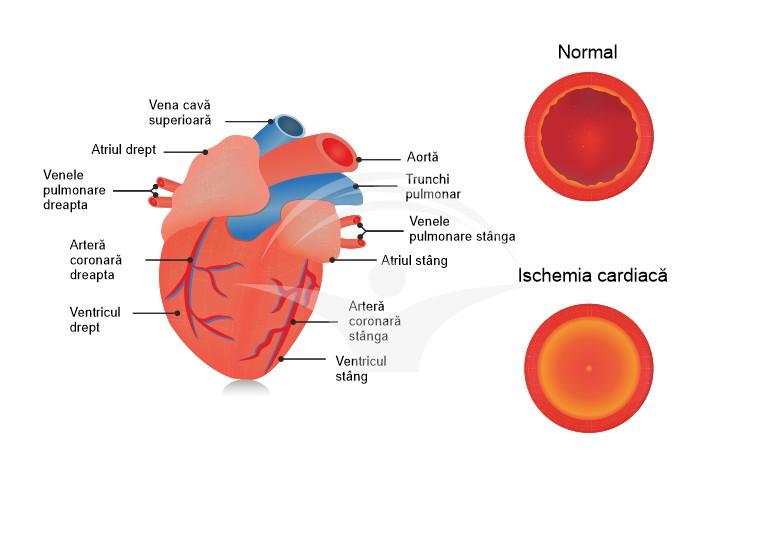

Cardiopatia ischemică se referă la un spectru de afecțiuni determinate de reducerea fluxului sanguin către mușchiul inimii, cel mai frecvent din cauza plăcilor de aterom care îngustează arterele coronare. Scăderea oxigenării miocardului poate genera simptome precum disconfort toracic sau lipsă de aer și poate evolua, în funcţie de gravitate, de la forme stabile până la sindroame coronariene acute; pe termen lung, afectarea repetată poate contribui la insuficiență cardiacă sau aritmii.

Procesele care stau la baza cardiopatiei ischemice sunt în principal legate de reducerea fluxului sanguin coronarian; ateroscleroza coronariană poate produce îngustări progresive ale arterelor și favorizează formarea placilor care pot ulceriza sau tromboza, reducând aportul de oxigen către mușchiul cardiac. În anumite situații, spasmul arterial sau disfuncţia microvasculară pot contribui la ischemie chiar în lipsa unor stenoze majore, iar dezechilibrele între cererea și oferta de oxigen (de exemplu în anemia severă sau la suprasolicitare) pot agrava tabloul clinic.